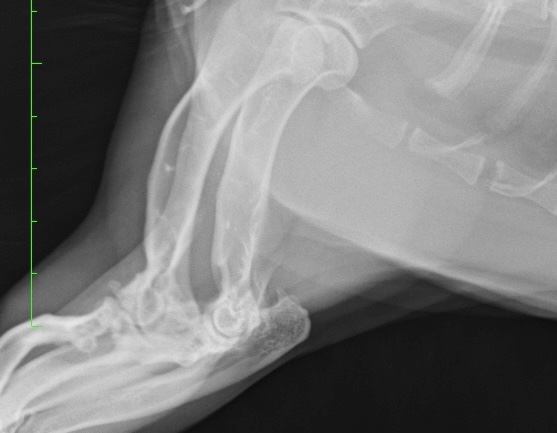

猫は後肢だけではなく前肢の肘や肩、手首(手根)にも関節炎が起き、慢性的な痛みによって日常生活に大きな支障がでることもあります。

またレントゲン検査では、骨や関節の変形が起きてからでないと異常が分からないことが多いため、こちらも関節炎の早期発見には不向きです。

視診、歩行検査、触診、整形外科的検査、レントゲン検査などを組み合わせて総合的に判断する必要があります。